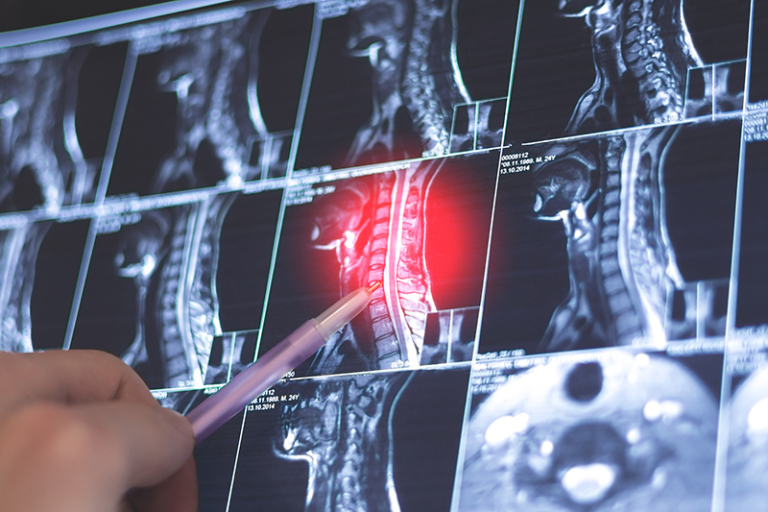

頭頸癌個案趨年輕!一文解構常見種類、症狀及預防關鍵

先說頭頸癌當中最普遍的鼻咽癌,不少名人明星,例如香港資深演員張達明、已故導演陳木勝以及韓國男星金宇彬都曾患上此症。鼻咽癌患者多會出現流鼻血、鼻塞、單側聽力下降或耳鳴等症狀,並出現頸部囊腫。目前已知鼻咽癌成因多與遺傳、感染艾巴氏病毒(EBV)有關,而常吃腌製類食品亦可能增加患病風險。

至於口腔癌、口咽癌及咽喉癌,則可能引起口腔持續潰瘍或咽喉部位的不適,包括喉嚨腫痛、吞嚥困難及耳痛等。成因除了與吸煙和飲酒有關,近年發現因性接觸引致的人類乳頭瘤病毒(HPV)感染,特別是HPV16型,亦是涉及口咽癌(包括扁桃體或舌根)的一大風險因素。而咽喉癌在本港雖不算普遍,惟著名荷里活影星韋基馬(Val Kilmer)、香港「金牌經理人」黃柏高皆受到此症困擾。

此外,若腫瘤患處涉及唾液腺,可能引致下巴下方或臉部腫脹;而若位於鼻竇,則可能引起鼻出血、鼻塞及慢性鼻竇感染等情況。